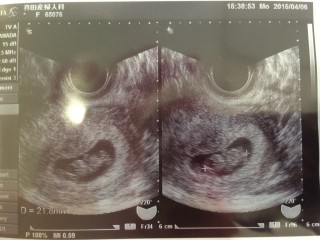

一気に人の姿になっていてビックリ! 8w6dだと思っていたら大きさから4日早まって9w3dになりました。 CRL22.1mm

二頭身になってぐにんぐにん動いていました。